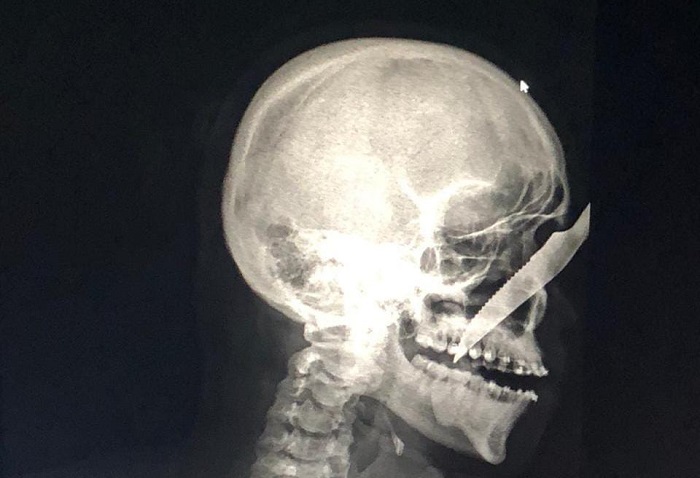

Jovem fica com faca cravada no rosto após ataque no Amazonas

Manaus – Alberto Carvalho de Oliveira, 25,  levou uma facada no rosto que ficou cravada no nariz na última sexta-feira (17). O autor da facada foi identificado como André Luís Benevides Carvalho, 35, que estava bêbado quando fez o ataque no município de Carauari (a 788 quilômetros a oeste de Manaus).